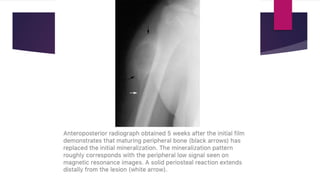

 Radiograph – “Dotted veil” calcification (confusing with

rhabdomyosarcoma or synovial sarcoma). There may be continuous or

discontinuous peripheral calcification.

 Zonation phenomenon – pattern of mineralization at periphery which is

more mature than central region that is still evolving. This differentiates

it from extraskeletal osteosarcoma.